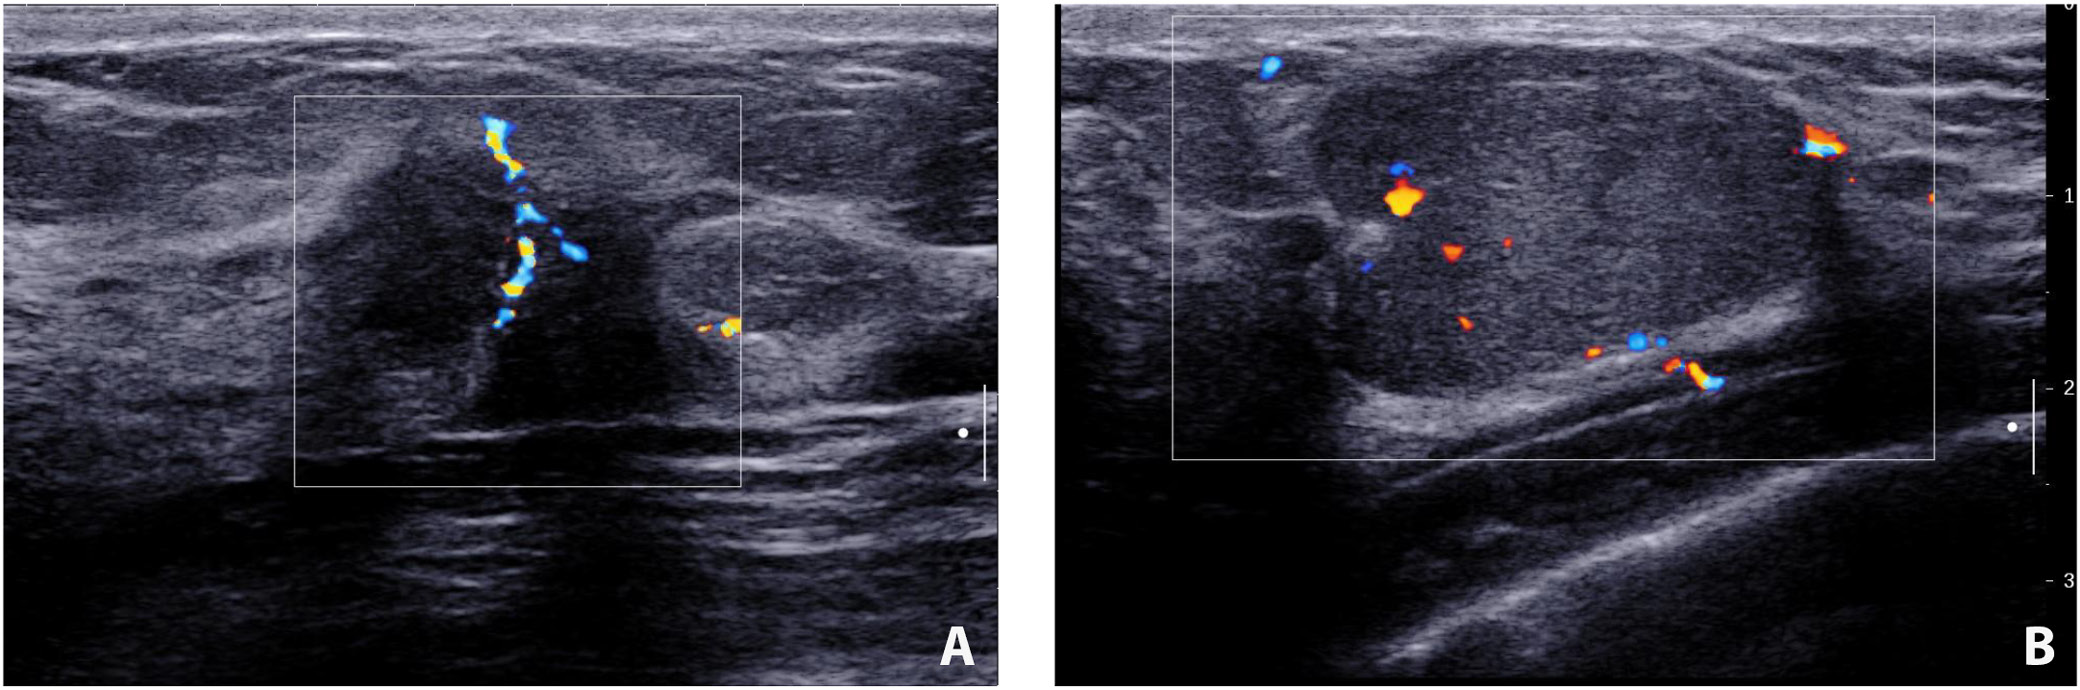

Ultrasound evaluation of breast lesions

The incidence of discovering a mass in the malignant cohort was higher than that in the benign group (37.1% vs 14.1%; χ2 = 6.97, df = 1, p = 0.008). It is also more likely to detect heterogeneous echogenicity in malignant lesions (45.7% vs 15.6%; χ2 = 10.58, df = 1, p = 0.001). Benign lesions tended to have well-defined borders (χ2 = 19.92, df = 1, p < 0.001) and regular shapes (χ2 = 11.25, df = 1, p = 0.001). Calcifications were more frequently detected in patients with malignant diseases (χ2 = 6.24, df = 1, p = 0.013). There was a higher proportion of malignant lesions showing posterior attenuation (42.9% vs 21.9%; χ2 = 4.81, df = 1, p = 0.028). Benign lesions were less likely to be associated with abnormal axillary node findings (76.6% vs 34.3%; χ2 = 17.01, df = 1, p < 0.001) (Table 3). The typical ultrasound images from the malignant and benign groups are shown in Figure 2.

Our results from the ultrasound evaluations underscore the salient differences between benign and malignant breast lesions. Previous literature highlights similar distinctions. The higher frequency of mass presentation in malignant lesions compared to benign ones (37.1% vs 14.1%) aligns with findings by Berg et al.,20 who emphasized that malignant masses are more prominently visualized on ultrasound. This observation of a higher proportion of cases with heterogeneity, calcifications and posterior attenuation in malignant lesions also matches the previous findings.21, 22, 23 Lastly, the markedly higher association of malignant lesions with abnormal axillary lymph node findings compared to benign lesions (65.7% vs 23.4%) reinforces the diagnostic importance of nodal assessment in breast imaging, as highlighted by Lee et al.24 In our study, we found the sensitivity, specificity, PPV, NPV, and AUC of ultrasonography to be 62.9%, 62.5%, 47.8%, 75.5%, and 0.627 respectively. The average diagnostic efficacy was lower than reported in studies,11, 25, 26 which could be due to geographic location and small samples in this study.